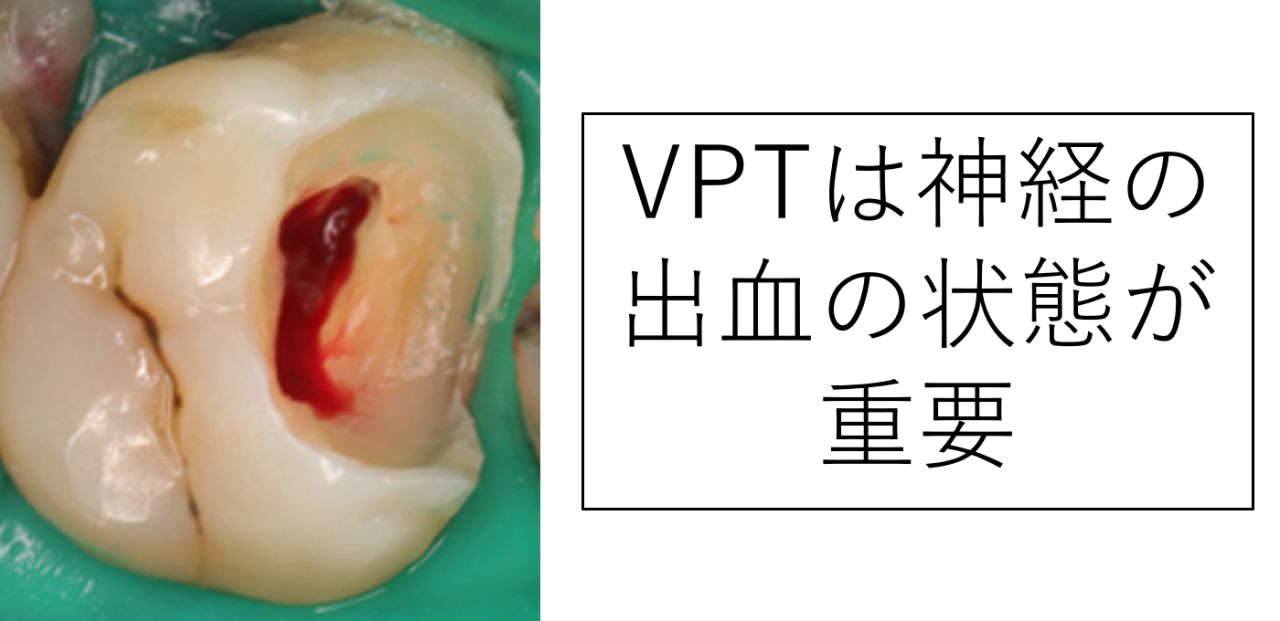

特に重要なのが「出血の状態」です。

虫歯を取り除いた後、神経から出血します。その出血が数分以内に落ち着くかどうかは、神経の炎症がどの程度かを示す重要な目安になります。

長時間止血できない場合は、炎症が広範囲に及んでいる可能性が高く、神経の保存は難しいと判断することがあります。

また、全く出血せず、腐った臭いや膿が出る場合は、神経が死んで機能していない可能性が高いです。死んだ神経かどうか見て判別できることもあります。この場合も神経を残すことは難しいと思われます。これらはレントゲンだけでわかるものではありません。

出血が短時間でコントロール(止血)できるということは、炎症が限局している可能性を示します。

止血ができないということは、神経の深い部分まで炎症が広がっている可能性があるということです。

VPTは「神経に回復力が残っていること」が前提となる治療です。そのため、止血の評価は非常に重要です。